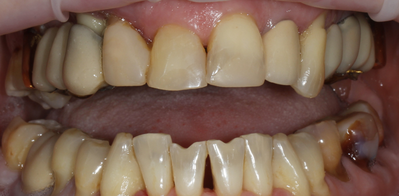

С чем обратился пациент:

Пациентка обратилась с жалобами на жевание и внешний вид зубов. На первый взгляд зубов было достаточно много. Но после диагностики стало понятно, что часть из них находилась под старым мостовидным протезом и была сильно разрушена. Эти зубы уже нельзя было восстановить - они подлежали удалению. Оставшиеся зубы также имели плохой прогноз: воспаления, подвижность, большие разрушения. Сохранять их не имело смысла, так как это не дало бы долгосрочного результата.